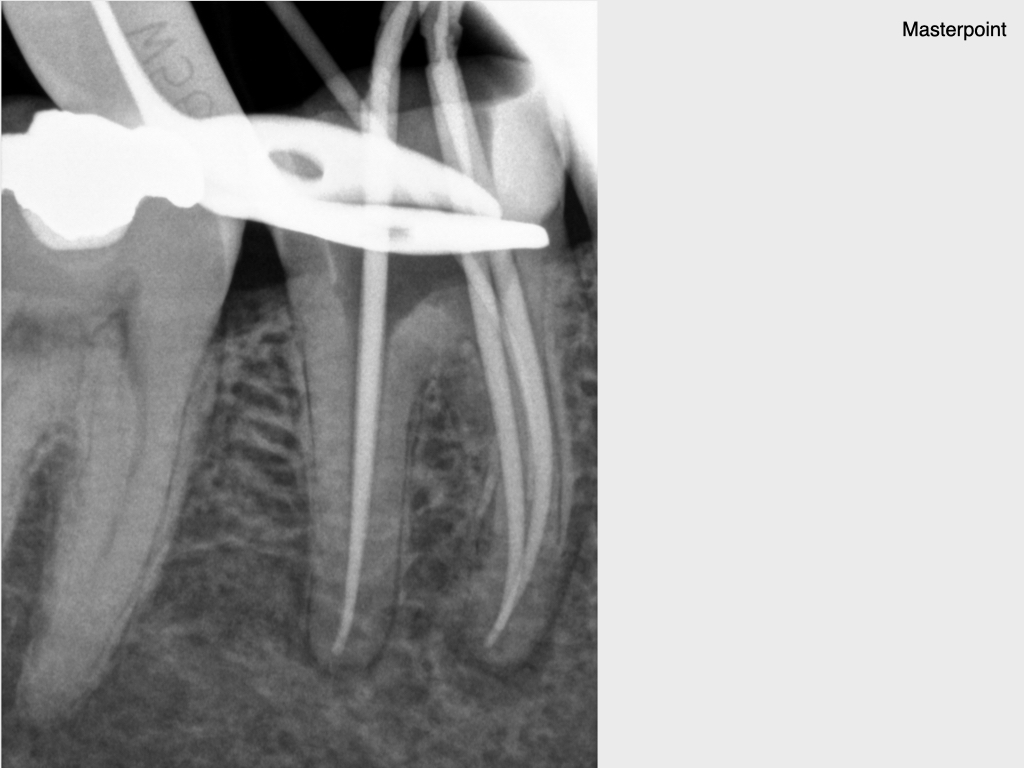

und wieder ein Fall aus der Reihe Pick, pick